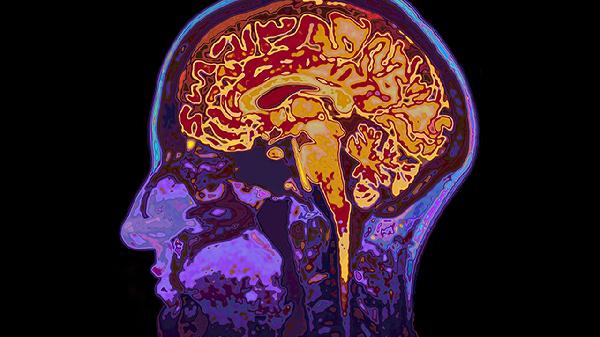

默认模式网络过度活跃与思维紊乱有关,任务正向网络激活不足导致注意力缺陷。前额叶-边缘系统连接异常影响情绪调控,感觉运动网络整合障碍可能引发知觉异常。神经网络整体效率降低影响信息处理速度。